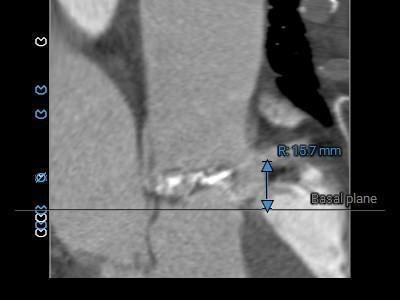

术前CT评估:

主动脉根部总览

重度钙化,分布于各窦内沿轴向延伸至窦底,无冠窦钙化延伸到LVOT水平

主动脉根部测量:

三叶式主动脉瓣,R-N疑似粘连,LVOT呈敞口型,非横位心。